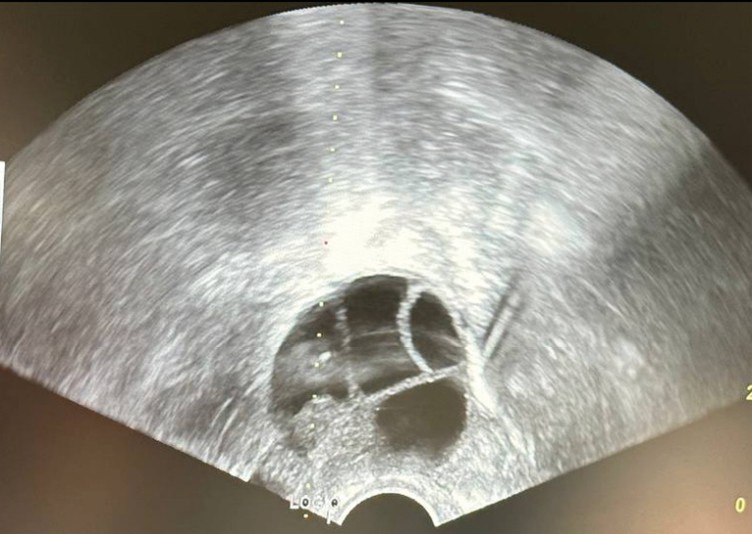

Ovarian stimulation was performed to retrieve oocytes in group 1. Initially, the procedure did not need to be linked to menstrual function because of the use of a random start protocol, i.e., ovarian stimulation was performed on any day of the cycle. A GnRH antagonist, recombinant follicle stimulating hormone, and human menopausal gonadotropin were used. The average duration of stimulation ranged from 10 to 12 days. GnRH or recombinant human chorionic gonadotropin was used to induce final oocyte maturation. Group 2 received no medication, but underwent an immediate transvaginal puncture (Fig. 3), so the average duration of this oncofertility program was 1–2 days.

Fig. 3. Ultrasound during transvaginal puncture (dashed line indicates ultrasound guidance)